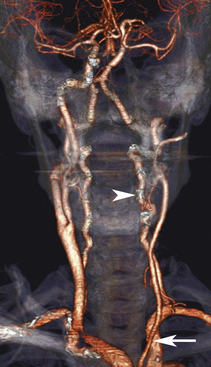

Хотя дуплексное ультразвуковое исследование заменило традиционную ангиографию в большинстве случаев для диагностики атеросклеротического заболевания сонных артерий и принятия решений относительно каротидной эндартерэктомии, результаты дуплексного ультразвукового исследования часто подтверждаются компьютерной томографической ангиографией (КТА) или магнитно-резонансной ангиографией (МРА). То же самое можно сказать и об оценке позвоночных артерий, поскольку эти методы продолжают развиваться ( рис. 11-16 ). Стеноз позвоночной артерии и внешняя компрессия позвоночной артерии костными структурами в областях V2 и V3 легко выявляются, особенно при контрастном усилении и трехмерной реконструкции изображения. Кроме того, фазово-контрастная МРА измеряет фактический кровоток в позвоночных артериях и непосредственно оценивает вертебробазилярную артериальную гемодинамику. С точки зрения затрат, дуплексное УЗИ остается лучшим выбором для оценки позвоночной артерии, но если есть сомнительные результаты ультразвукового исследования, для получения необходимой диагностической информации может потребоваться трехмерная КТА или МРА с контрастным усилением. В частности, когда результаты дуплексного ультразвукового исследования предполагают обструктивное заболевание позвоночной артерии в месте, недоступном для прямой визуализации, например, недоступное начало позвоночной артерии или форма волны потока с высоким сопротивлением, характерная для более дистального (области V3 или V4) заболевания, эти методы возможность визуализировать интересующую область с минимальной инвазивностью. Ограничения МРА для позвоночных артерий во многом такие же, как и для системы сонных артерий. Не все пациенты являются кандидатами на магнитно-резонансную процедуру из-за металлических имплантатов или неспособности полностью сотрудничать во время обследования. Процент таких больных увеличивается с увеличением возраста; к сожалению, растет и заболеваемость цереброваскулярными заболеваниями, затрагивающими вертебробазилярную систему. Пропадание сигнала в областях сильной турбулентности потока, например, дистальнее стеноза или в области очень медленного потока, как это можно наблюдать в гипоплазированном сосуде, также в некоторых случаях ограничивает диагностические возможности МРА ( рис. 11-17 ). . КТА обеспечивает изображения заднего кровообращения с высоким разрешением у пациентов без противопоказаний к йодсодержащему контрастному веществу или нарушения функции почек. Современные алгоритмы реконструкции позволяют вычитать мягкие ткани и костные структуры, чтобы обеспечить изображения экстракраниального и внутричерепного кровообращения с высоким разрешением.

РИСУНОК 11-17. Магнитно-резонансная ангиография (МРА) позвоночных артерий. МРА дуги аорты показывает как проксимальную часть общей сонной артерии (С), так и проксимальную часть левой позвоночной артерии (маленький наконечник стрелки) . Правая позвоночная артерия (стрелки) гипоплазирована, кровоток резко снижен и, следовательно, плохо просматривается. Обратите внимание на стеноз левой подключичной артерии (S) (большой наконечник стрелки) и постстенотическое расширение. Поскольку этот стеноз лежит за пределами позвоночного происхождения, он не влияет на кровоток в позвоночной артерии.